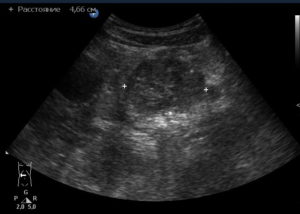

Но более информативным методом диагностики является ультразвуковое исследование. Одним из важных диагностических признаков в этом случае являются диффузные изменения железы. Контуры органа при этом могут быть неровными, а ее размеры, как правило, находятся в пределах нормы.

Фиброз поджелудочной железы не является самостоятельным заболеванием. Этим термином обозначают патологические изменения органа, которые обычно являются признаком хронического панкреатита. Фиброз определяется на УЗИ. Как правило, он не сопровождается симптомами, поэтому становится случайной находкой врачей при плановом обследовании пациента.

Клинических признаков фиброз не имеет. Его можно увидеть на УЗИ. Замещение паренхимы соединительной тканью видит патологоанатом при вскрытии больного. А вот определить фиброз по симптомам нельзя.

Виден ли фиброз печени на УЗИ?

При проведении диагностики получить однозначный ответ на вопрос о том виден ли фиброз печени на УЗИ невозможно. Поскольку изменение эхогенности и структуры органа может происходить при других заболеваниях, его можно легко спутать с другой болезнью.

Как определить фиброз по УЗИ?

Зачем проводят ультразвуковую диагностику и как определить фиброз по УЗИ, спросите вы? Распознать патологический процесс в паренхиматозном органе можно только по косвенным признакам. У пациентов с дегенеративным заболеванием печени наблюдается: асцит, изменение кровотока в воротной вене и увеличение размеров самого органа.

Важный метод диагностики фиброза поджелудочной железы – ультразвуковое исследование органов брюшной полости (УЗИ брюшной полости). Определяется диффузное повышение эхогенности органа, структура неоднородная, размеры уменьшены; возможно выявление расширения вирсунгова протока.

Более информативна эндоскопическая ультросонография, которая позволяет выявить линейные тяжистые включения разной протяженности и формы, бугристость контуров, гиперэхогенность паренхимы. При проведении ЭРХПГ выявляются изменения протокового аппарата, вызванные образованием рубцов.